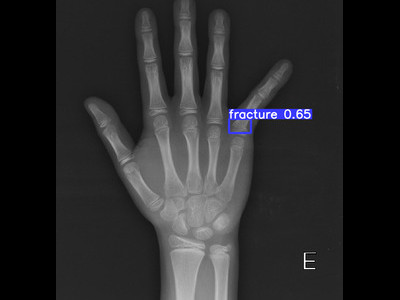

Detecção de fratura da falange proximal em Raio X

Fratura da falange proximal